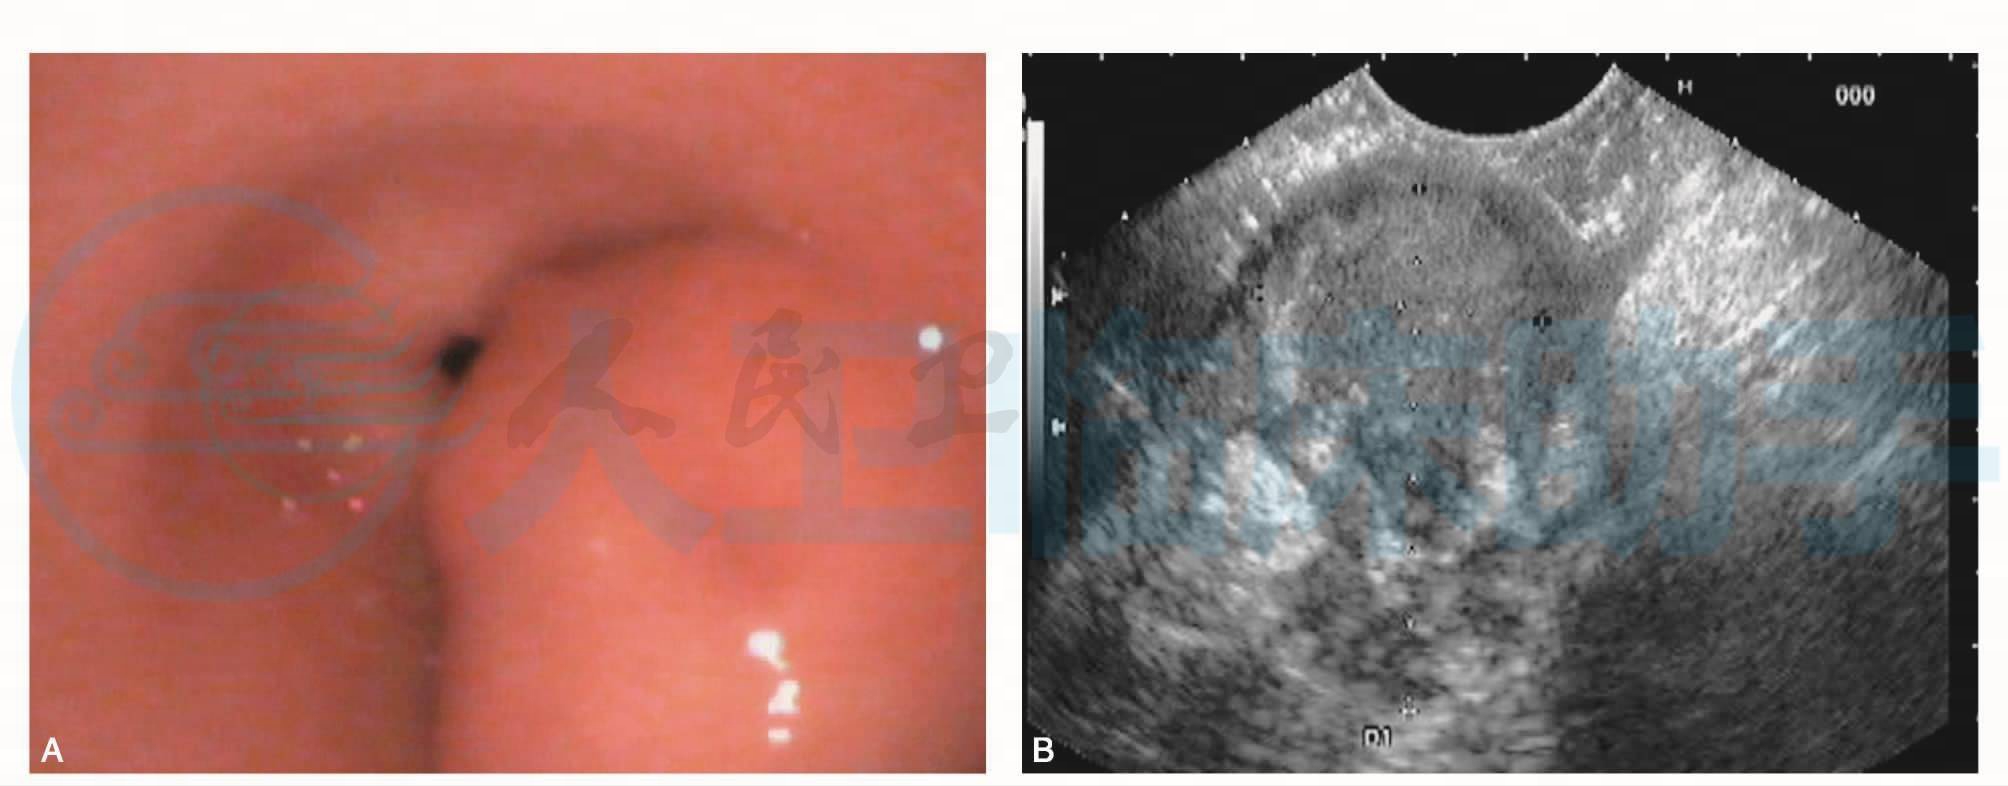

内镜超声(图1):探头置于胃窦隆起处扫查,见胃壁超声第三、四层结构内混合回声肿块,内部回声不均,见有分隔改变,超声切面大小约36mm×20mm,余胃壁结构清晰、完整。

图1 内镜超声

A.胃窦大弯延至近幽门处见一隆起性病变,表面光滑;B.胃壁超声第三、四层结构内混合回声肿块